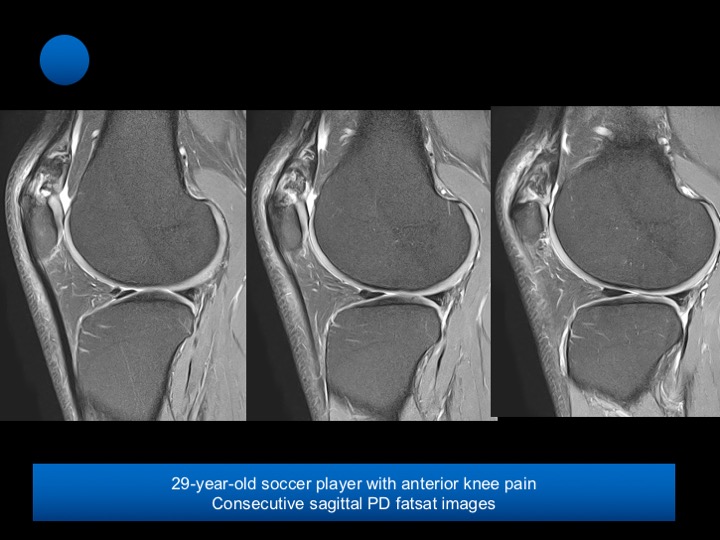

29-year-old soccer player with chronic anterior knee pain

Bipartite patella is a developmental variation in which peripheral, accessory ossification centers fail to fuse with the main body of the patella. While at least three different locations of bipartite patella have been described, it typically involves the superolateral aspect of the patella, at the insertion of the vastus lateralis muscle, is seen in approximately 2% of the population, and is almost always bilateral. Bipartite patella is more common in males tan females by a ratio of 9:1.

Bipartite patella is usually asymptomatic and is an incidental finding on radiographs. Only 2% become symptomatic and painful. The majority of painful bipartite patella are reported in young men who are actively involved in sporting activities.

Occasionally, in response to overuse or less common an acute injury, a synchondrosis may become either partly or completely disrupted, allowing abnormal motion, friction, and subsequently the development focal degenerative changes, and edema.

The most common presentation is with anterior knee pain on most activities involving extension of the knee. Reference article.